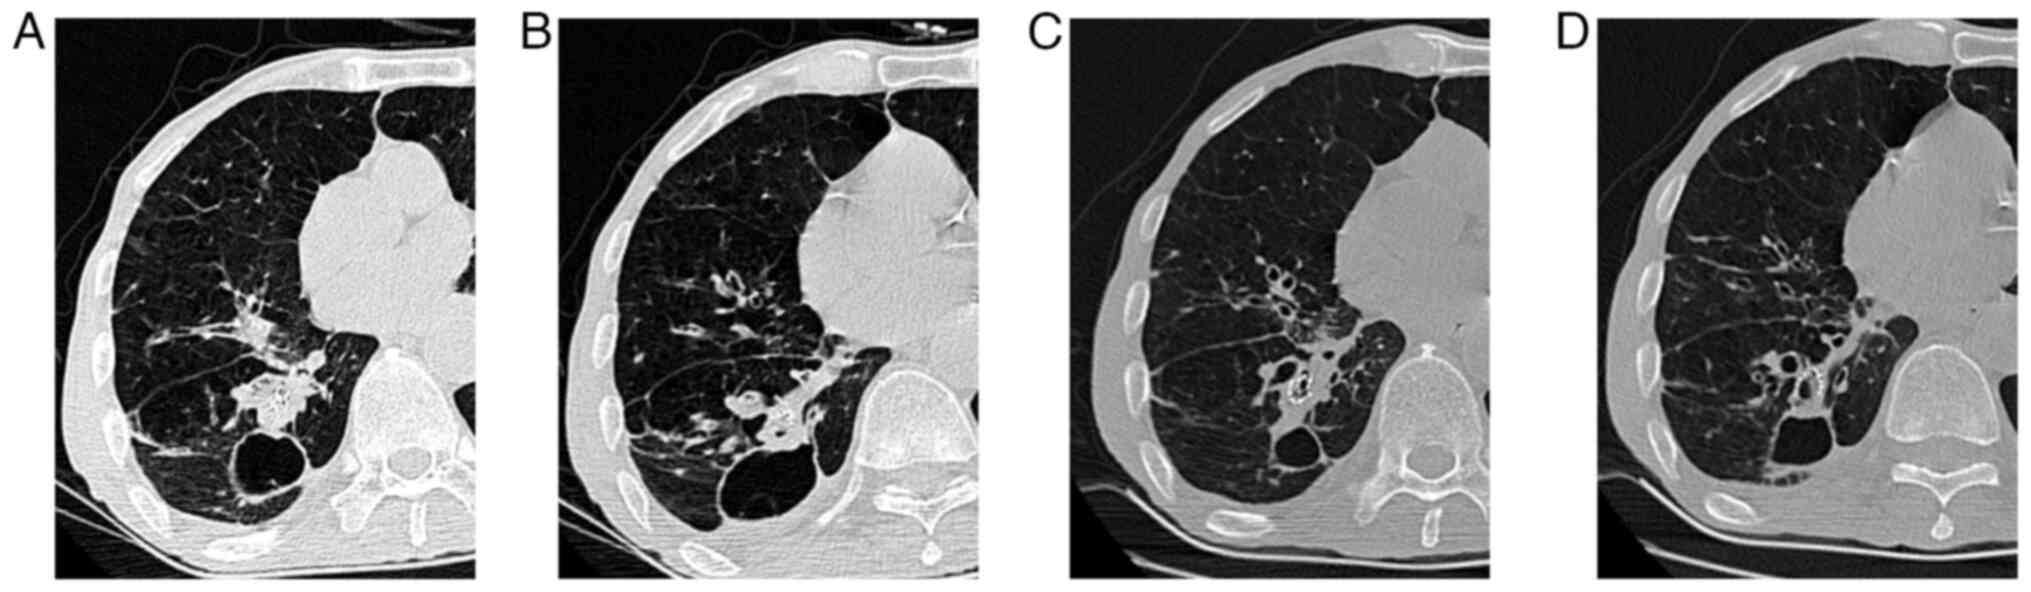

Prior to MWA, the patient received 100 mg pethidine intramuscularly. Subsequently, the patient was placed into the prone position and 1% lidocaine was injected locally into the pleural wall layer by layer. A total of two ECO-100al5 MWA needles were used, which were connected to the ECO-100a1 MWA system [ECO Medical Technology (Nanjing) Co., Ltd.]. The procedure involved a double-needle ablation approach, according to the manufacturer's guidelines (Fig. 3A and B). Needle 1 received 45 W radiation for 2 min, while needle 2 was treated with 45 W radiation for 2 min, followed by 50 W radiation for 3 min. A water circulation cooling system was used to maintain stable the surface temperature of the ablation needle. Prior to MWA, the revocation pathway was ablated, while immediate chest examination revealed right pneumothorax (Fig. 3C), necessitating closed thoracic drainage due to air bubbles observed during coughing. At six days following MWA, significant subcutaneous emphysema was detected in the neck and chest, with chest CT scan showing enlarged ablation and ground glass areas alongside a small pneumothorax with pleural effusion (Fig. 4A). By day 14, the patient experienced fever, cough with yellow purulent sputum, signs of pulmonary infection and encapsulated pleural effusion on chest CT scan (Fig. 4B). Therefore, the patient was administered ceftazidime (2.0 g twice daily) as an anti- microbial therapy. At 35 days after MWA, chest CT scan revealed encapsulated effusion in the right lower pleural cavity, gas-fluid flat and a 3-mm BPF in the posterior basal A subsegment bronchus (B10a) of the right lower lobe (Fig. 4C). Drainage was performed, while air bubbles and purulent fluid were observed during coughing and speaking. Pseudomonas aeruginosa was isolated from sputum and pleural effusion cultures. At 37 days following MWA, methylene blue was injected via bronchoscopy into the thoracic drainage tube. The results verified the presence of BPF (Fig. 5A and B), thus leading to the implantation of an EBV (EBV-TS-5.5; Pulmonx Corp.) in the right inferior lobe posterior basal segment bronchus (B10) at 45 days after MWA (Fig. 6A and B). EBV implantation markedly reduced air leakage, which was entirely stopped five days after implantation, thus allowing the removal of the thoracic drainage tube (Fig. 7A and B). Furthermore, at day 86 after EBV implantation, chest CT scan revealed that the pulmonary infection and narrowed pulmonary necrotic cavity had resolved (Fig. 7C and D; Table I). No serious complications were recorded at 6-month follow-up.

Figure 4

Evolution of the chest CT following MWA. (A) CT image at six days after MWA. (B) CT image at 14 days after MWA showing severe pulmonary infection. (C) CT image showing bronchopleural fistula (red arrow). CT, computed tomography; MWA, microwave ablation.